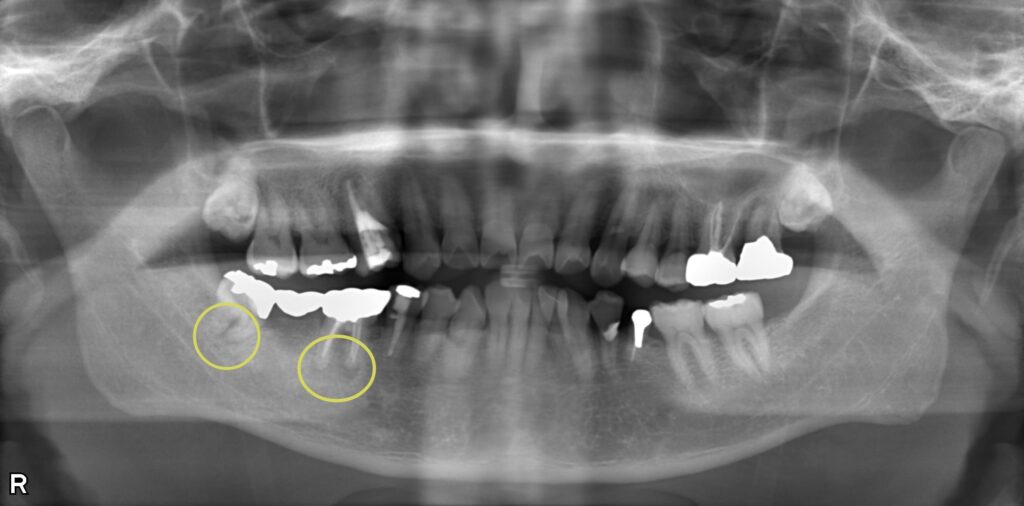

根管感染と虫歯を併発した複合症例の治療

右下がジンジンする、噛んでも磨いても痛いとのことで来院されました。 右下6番は根管内に感染を起こして透過像があり、右下8番は被せ物の中で虫歯になっていて、神経の炎症を引き起こしていました。 まず8番の抜髄処置を行い、緊密に根管充填したのち、6番の治療にも取り掛かりました。 どちらの歯も複雑な根管形態をしていたため、マイクロスコープを使用して丁寧に根管内を清掃しました。 術後の経過は良好で、透過像も消失しています。

| 概要 | 右下がジンジンする、噛んでも磨いても痛いとのことで来院されました。 右下6番は根管内に感染を起こして透過像があり、右下8番は被せ物の中で虫歯になっていて、神経の炎症を引き起こしていました。 まず8番の抜髄処置を行い、緊密に根管充填したのち、6番の治療にも取り掛かりました。 どちらの歯も複雑な根管形態をしていたため、マイクロスコープを使用して丁寧に根管内を清掃しました。 術後の経過は良好で、透過像も消失しています。 |

| 治療部位 | 右下6番、8番 |

| 治療内容 | 根管治療 |